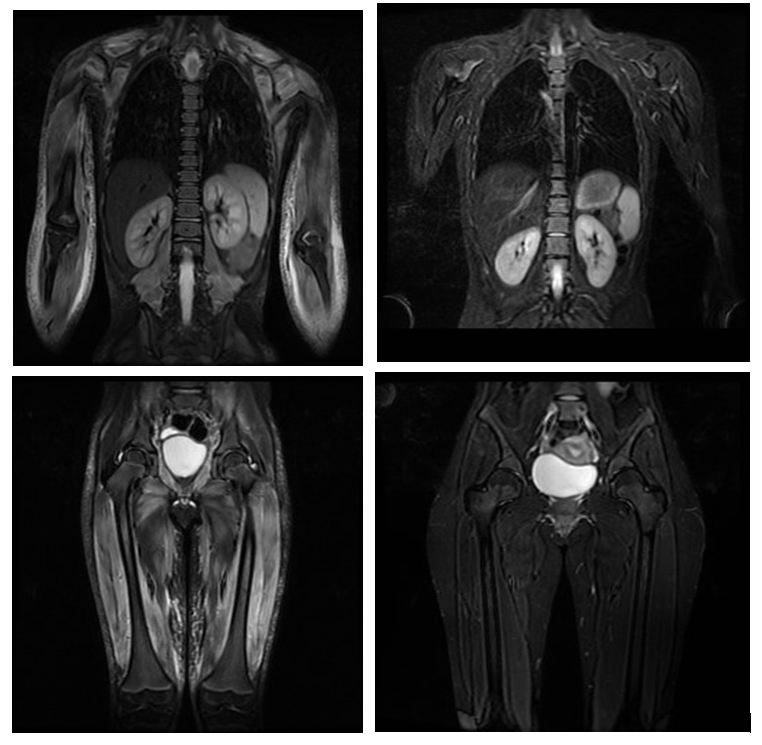

3. Resonancia magnética muscular:

La resonancia magnética (RM) es una prueba de diagnóstico por la imagen que permite valorar de forma indirecta la presencia de inflamación muscular. Se realiza con el paciente tumbado precisando que el niño/a no se mueva durante el tiempo en el que se toman las imágenes. No radia, no precisa la administración de contraste, pero la duración habitual es de 30-45 minutos por lo que, en los casos de menor edad puede ser necesaria la sedación del paciente. Se puede realizar de una zona determinada del cuerpo o corporal total, permitiéndonos valorar la extensión de la inflamación. La resonancia ha permitido comprobar la afectación de músculos que inicialmente se creían respetados como la musculatura distal de extremidades (más alejada del tronco). Por ello, podemos afirmar que la DMJ es una miopatía de predominio pero no exclusiva proximal.

Permite valorar músculo, fascia y tejido celular subcutáneo y detectar inflamación en músculos clínicamente no afectados. Es una prueba objetiva que permite diferenciar actividad de daño muscular y que se normaliza con el tratamiento, por lo que es una herramienta útil en el seguimiento del paciente. Además, tiene valor pronóstico, al haberse descrito relación entre la afectación del tejido celular subcutáneo con el desarrollo de calcinosis.

El principal problema es que en el momento actual no existen protocolos estandarizados de secuencias ni una única escala de valoración de resonancia. Distintos grupos de investigación están trabajando en este sentido con el fin de homogeneizar la práctica clínica.